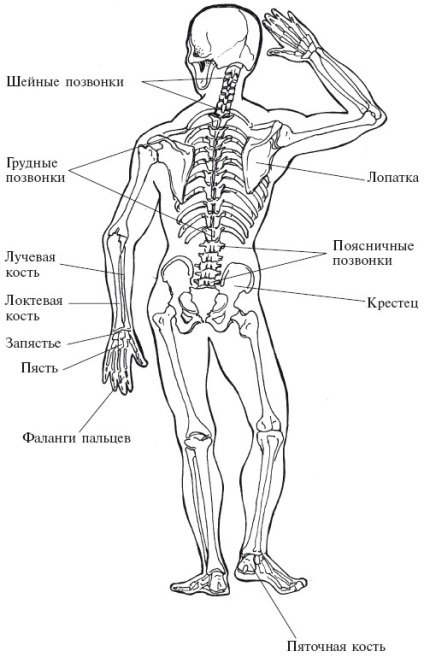

A csontváz szerkezet

A gerincoszlop - a fő pillére az emberi szervezetben. Támogatja a lágyabb része a test és ad a test a kívánt formát.

újszülött csontváz áll 350 csontokat. Nőnek a fejleményekről, és a csontváz egy felnőtt már 260 csontokat.

A gerincoszlop tartalmaz 26 üreges hengeres csontok - csigolyák. [24 egyedi üreges 7, és a nyaki, mellkasi és 12 ágyéki 5; plusz keresztcsonti (amely 5 kondenzált csigolyák) és farkcsont (4 áll intergrown). Összesen 33 csigolyák.]

Ahhoz, hogy a tetején a gerinc csatolt koponya. Ő 29 lapos csontokban. Kerek rész (nevezetesen azt, mint tudja, az agy) áll 8 csontok, az arc, valamint az alsó állkapocs - 14 csontok, vannak csontok a fül - három-három, és egy csont a torkán (hyoid).

A csontok az emberi test (elölnézet)

test csontváz, a csontok és az ízületek. Itt van egy emberi csontváz, hogy formálja a teljes test csont Helyek vegyületeket nevezzük ízületek; Pontosan az ízületek, különösen a váll, könyök, csukló, csípő, térd, boka, láb, gerinc letétbe szervetlen anyagok elfogyasztott élelmiszer és az ivóvíz. Ezek a lerakódások okoznak éles fájdalom, korlátozott mozgása az ízületek, ami a csontosodási az egész test. A legtöbb ember azt hiszi, hogy az ok a kor.

A csontok az emberi test (hátulnézet)

A mellkas tartalmaz 25 csontok: egy szegy - a szegycsont és a bordák 24. A felső hét pár borda van hátulján a gerinc, és az első - a szegycsont. A következő három pár egyesítjük csak a gerinc, és lekerekített elülső hogy a szegycsont. A két pár alsó úszó bordák nem is éri el az első része a mellkas. két kulcscsontból felett a bordák. Front, melyhez kapcsolódnak a szegycsont és a hátsó - a pengék. Minden kéz áll egy felkarcsont, és a két alkar csontjai - ulna és sugarát.

Nyolc csukló csontok formájában. A többi öt csontok - lábközép - csatlakoztassa a csukló és az ujjak. A csontokat alkotó ujjak nevezzük ujjperceket. A hüvelykujj a két, a másik 4-3. Így az egyik kéz ujjai tartalmaz 14 ujjperceket.

Keresztcsont és farkcsont - a legszélesebb része a gerinc. Ezek a kapcsolódó hosszú, izmos teste és nehéz csontok - a combcsont. A combcsont csatlakozik a két alsó lábszár csont - a nagy és fibula - a szalagok. Csomagok védelem alá tartozó a térdkalács.

Boka (tarsus) áll a hét csontok. A méret jobban mint a csontokat a csuklóját. láb íve - lábközépcsont - hozzon létre öt csontok, ami egyrészt kapcsolódik a boka, másrészt - az ujjak. A lábujjak is 14 ujjperceket.